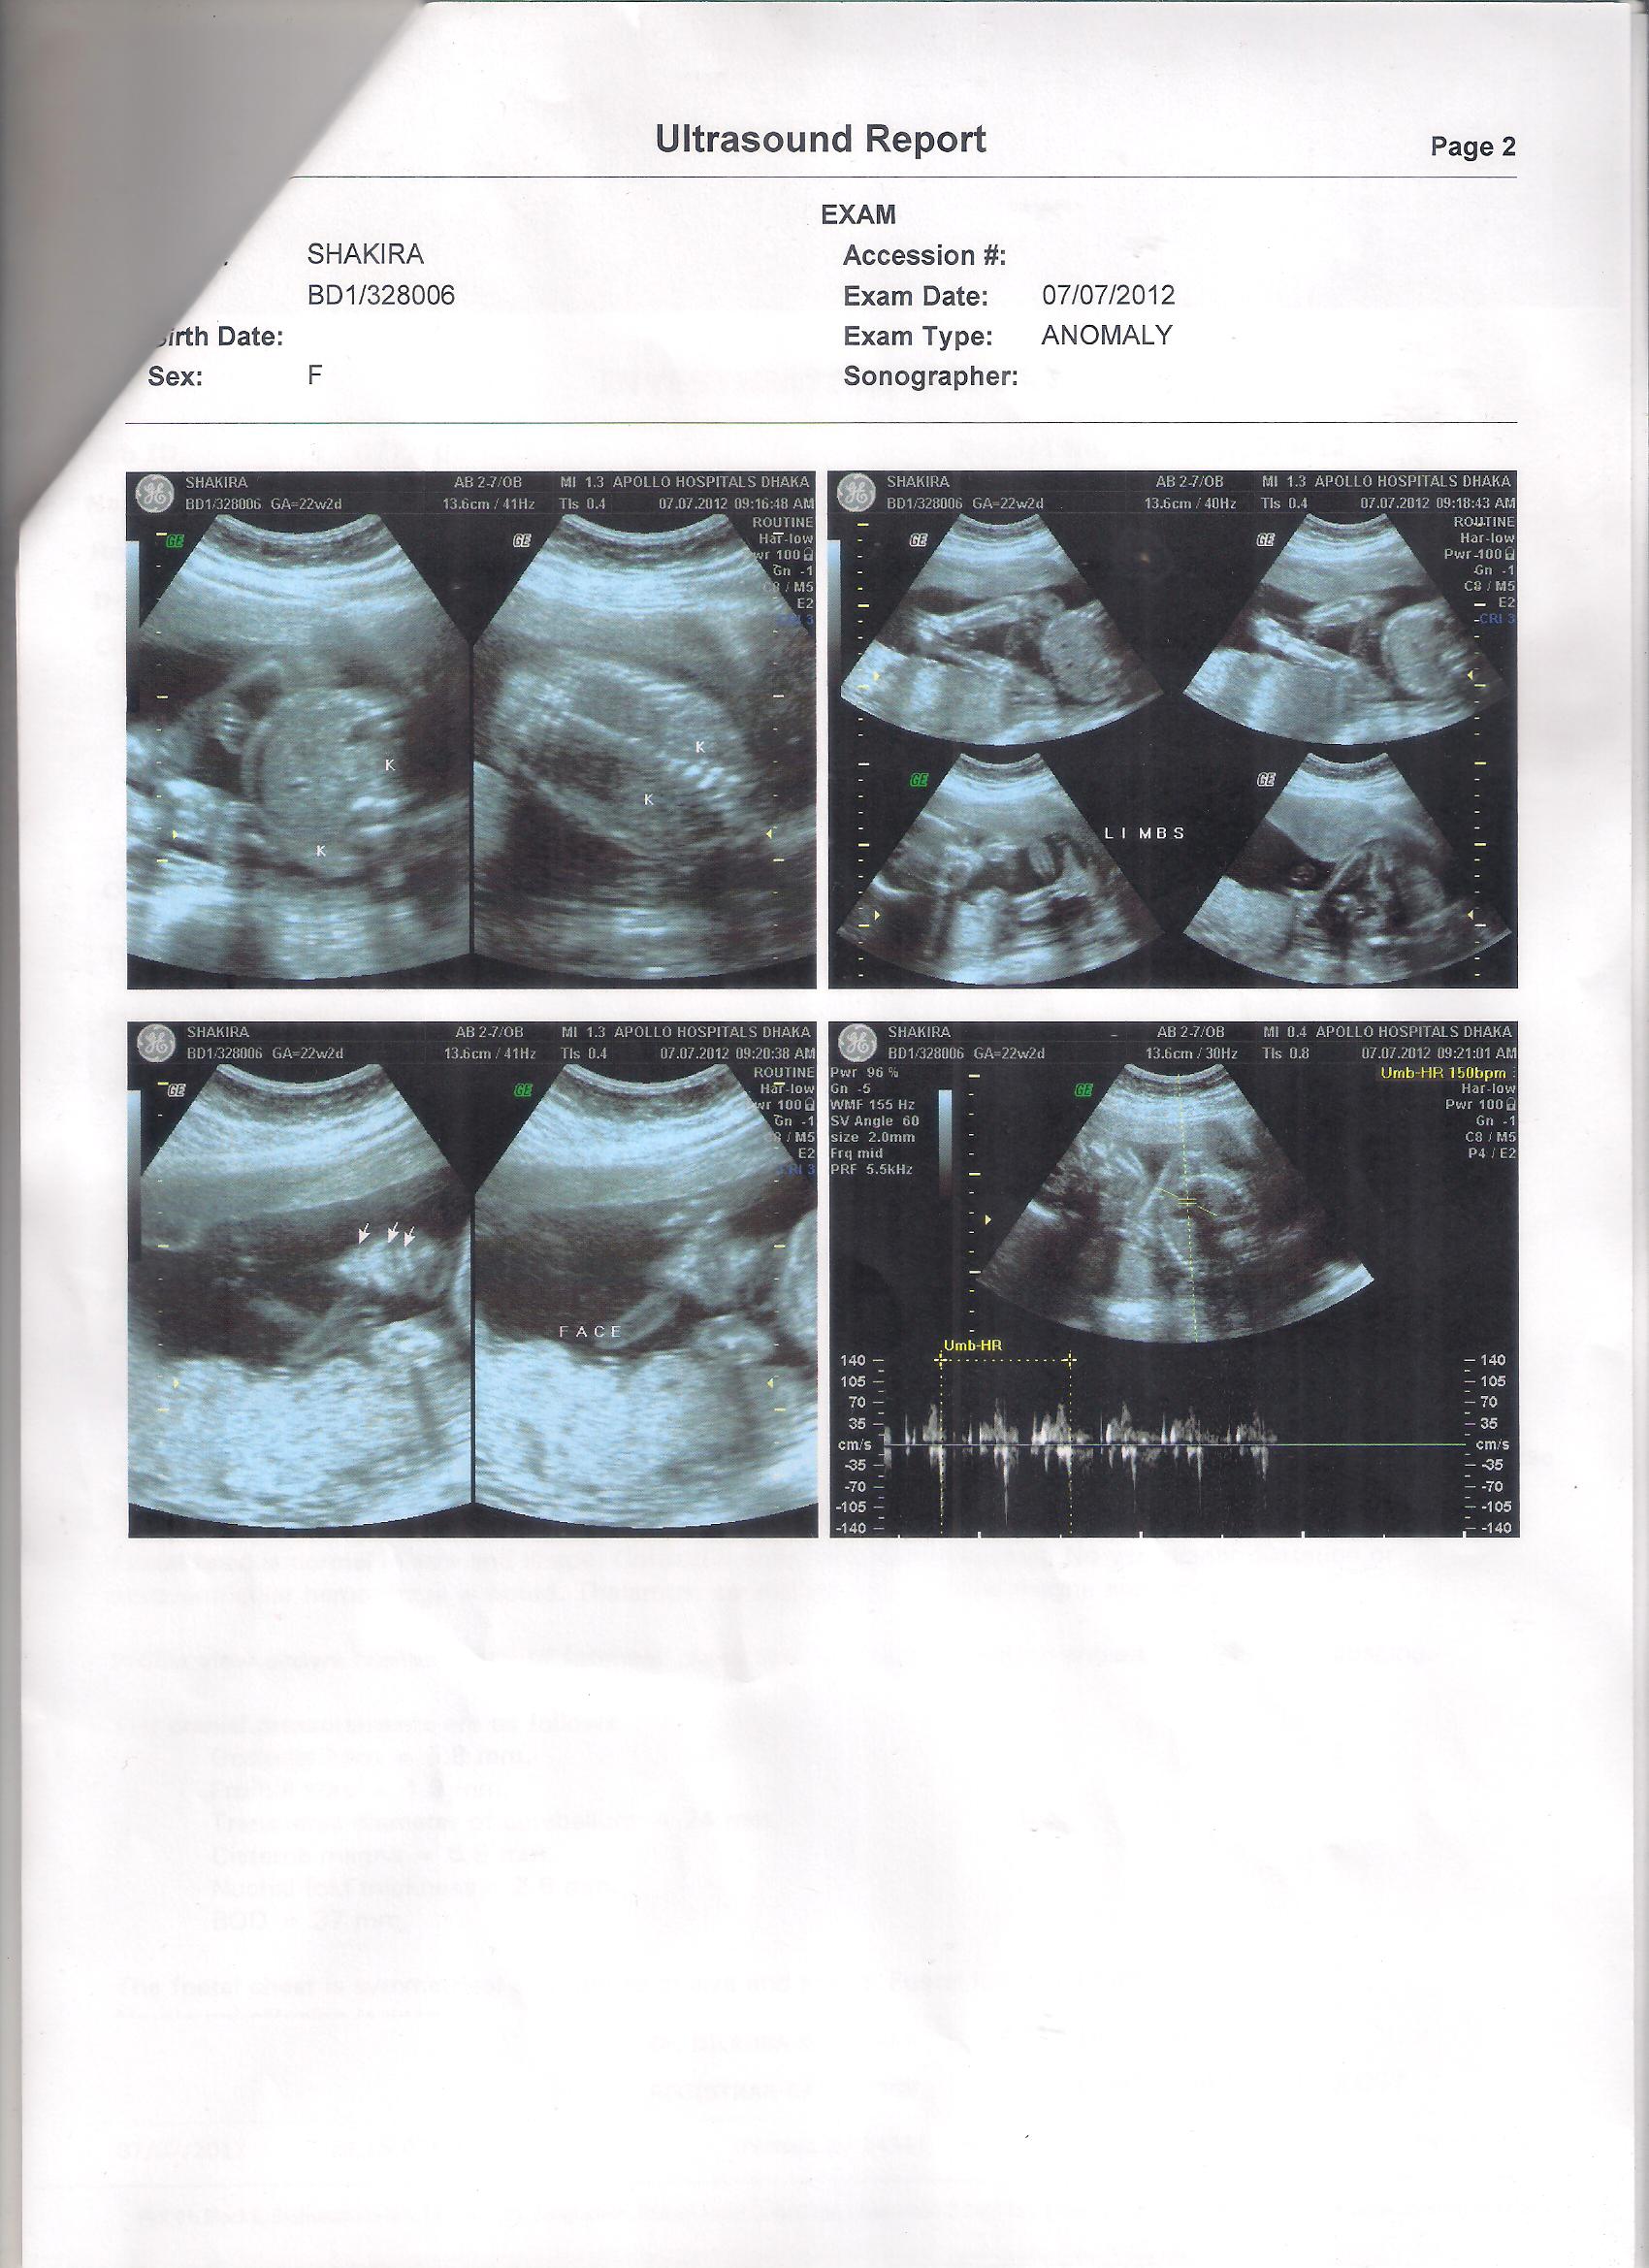

Attachment 4013Attachment 4014Attachment 4015

Sorry Razi, I'm not good at all with ultrasounds, I never manage to figure out how baby is positioned let alone seeing his/her genitals or the nub. I always wonder how other girls manage to figure it out! But other girls will be able to help you. Are you swaying pink or blue? good luck with having the baby of your dreams!!